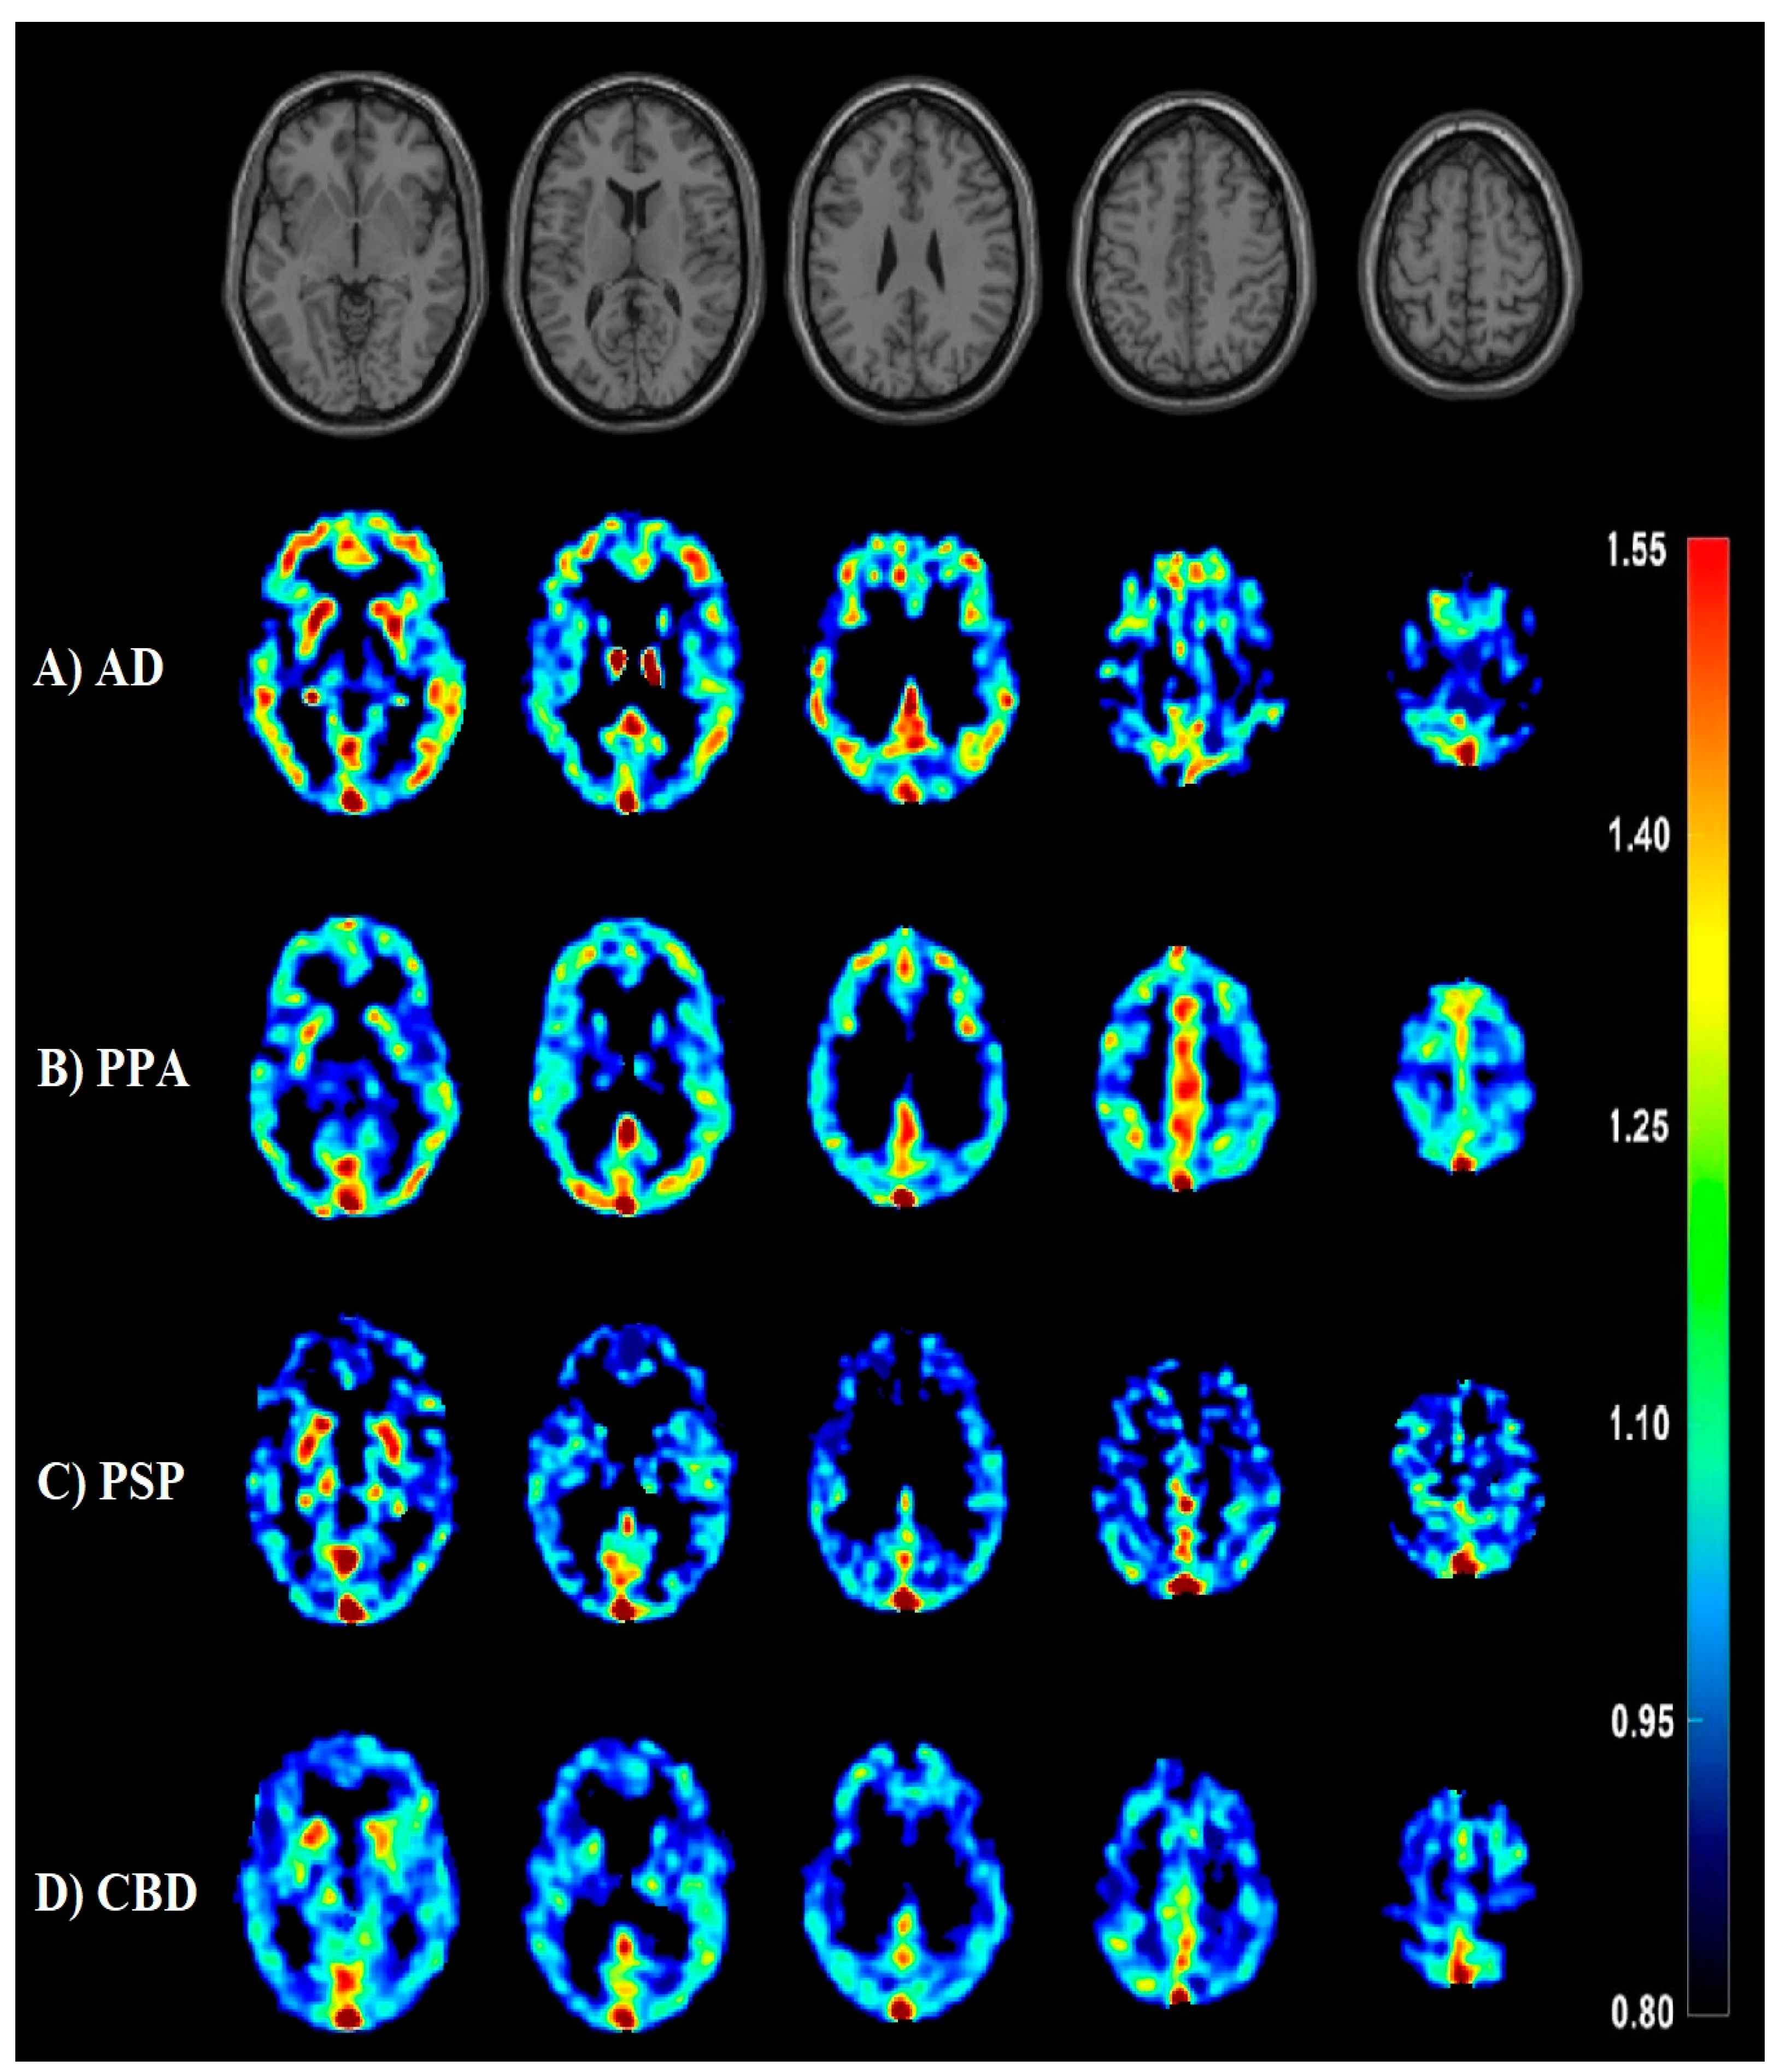

- Minoshima, S.; Cross, D.; Thientunyakit, T.; Foster, N.L.; Drzezga, A. 18F-FDG PET Imaging in Neurodegenerative Dementing Disorders: Insights into Subtype Classification, Emerging Disease Categories, and Mixed Dementia with Copathologies. J. Nucl. Med. 2022, 63, 2S–12S. [Google Scholar] [CrossRef]

- Nestor, P.J.; Altomare, D.; Festari, C.; Drzezga, A.; Rivolta, J.; Walker, Z.; Bouwman, F.; Orini, S.; Law, I.; Agosta, F.; et al. Clinical utility of FDG-PET for the differential diagnosis among the main forms of dementia. Eur. J. Nucl. Med. Mol. Imaging 2018, 45, 1509–1525. [Google Scholar] [CrossRef]

- Jang, Y.K.; Lyoo, C.H.; Park, S.; Oh, S.J.; Cho, H.; Oh, M.; Ryu, Y.H.; Choi, J.Y.; Rabinovici, G.D.; Kim, H.J.; et al. Head to head comparison of [18F] AV-1451 and [18F] THK5351 for tau imaging in Alzheimer’s disease and frontotemporal dementia. Eur. J. Nucl. Med. Mol. Imaging 2018, 45, 432–442. [Google Scholar] [CrossRef] [PubMed]